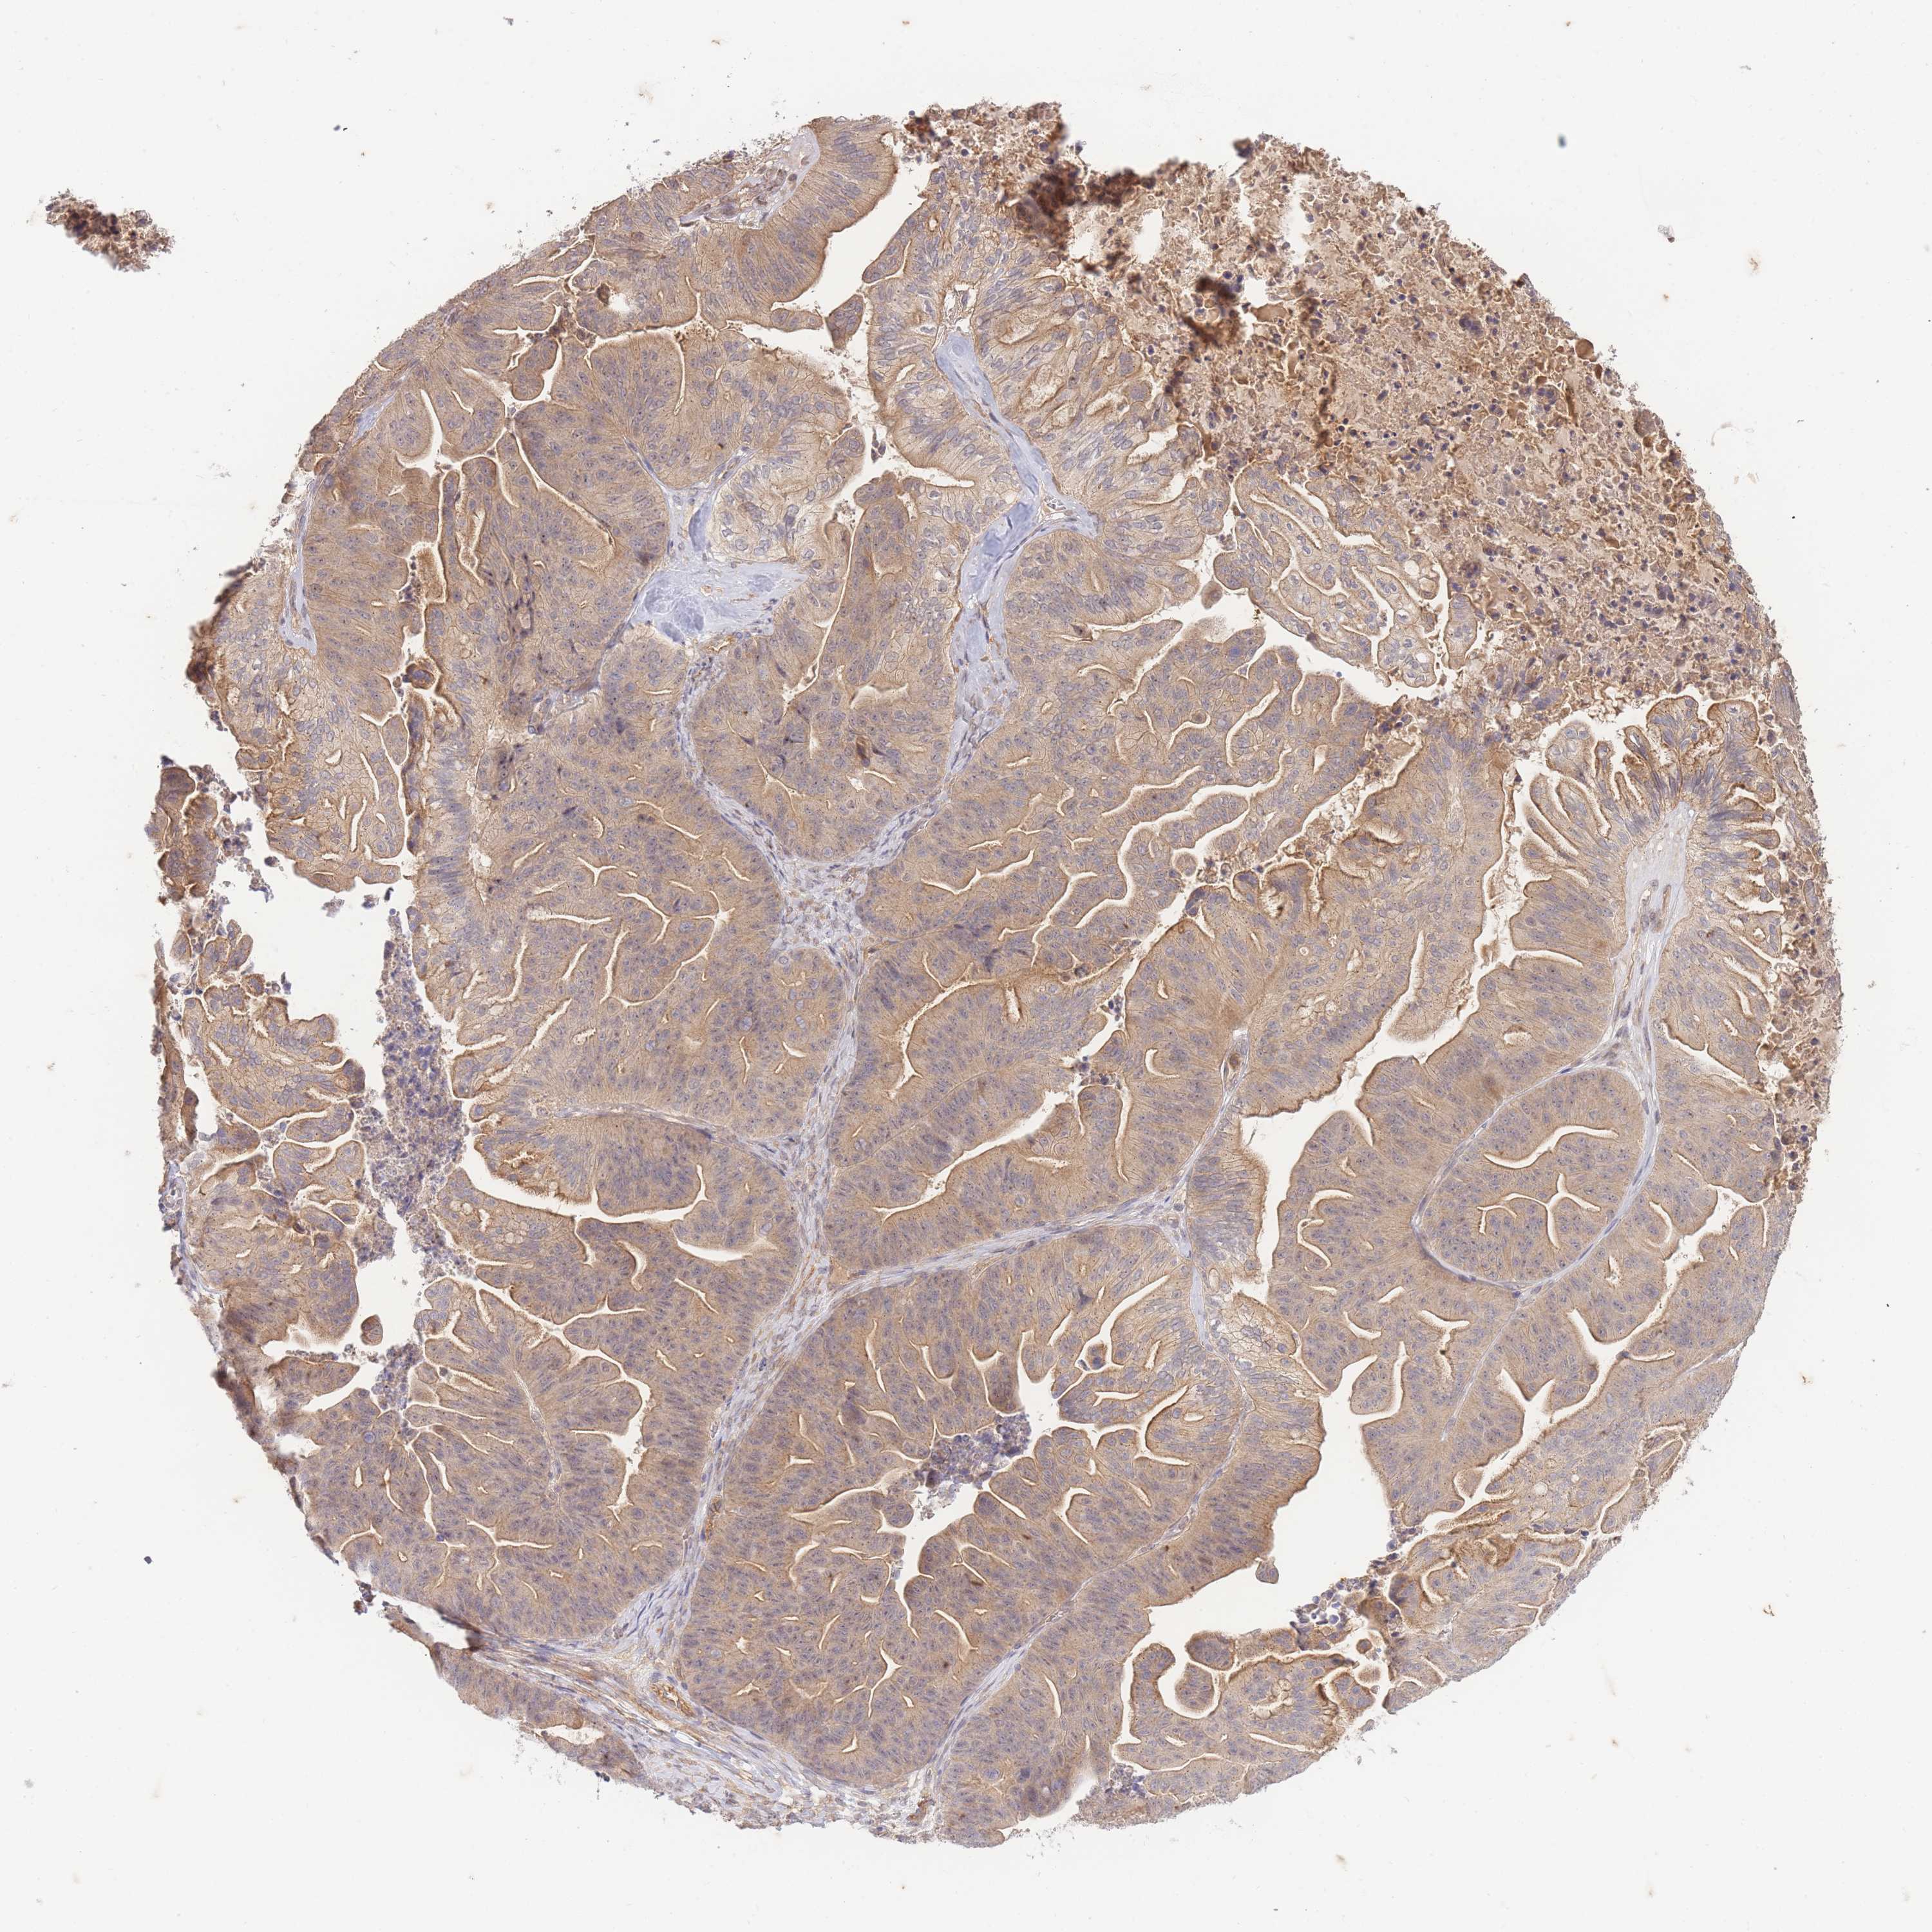

OVARIAN CANCER - Protein expressioni

A mouse-over function shows sample information and annotation data. Click on an image to view it in a full screen mode. Samples can be filtered based on level of antibody staining by selecting one or several of the following categories: high, medium, low and not detected. The assay and annotation is described here.

Note that samples used for immunohistochemistry by the Human Protein Atlas do not correspond to samples in the TCGA dataset.

Antibody stainingi

Antibody staining in the annotated cell types in the current human tissue is reported as not detected, low, medium, or high, based on conventional immunohistochemistry profiling in selected tissues. This score is based on the combination of the staining intensity and fraction of stained cells.

Each image is clickable and will lead to virtual microscopy that enables deeper exploration of all samples and also displays staining intensity scores, fraction scores and subcellular localization as well as patient and tissue information for each sample.

Antibody HPA051126

Staining

High

Medium

Low

Not detected

Intensity

Strong

Moderate

Weak

Negative

Quantity

>75%

75%-25%

<25%

None

Location

Nuclear

Cytoplasmic/membranous

Cytoplasmic/membranous,nuclear

Cystadenocarcinoma, serous, NOS

Carcinoma, NOS

Cystadenocarcinoma, mucinous, NOS

Carcinoma, endometroid